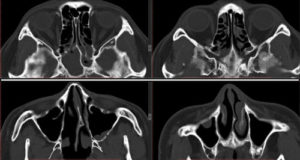

Нередко, особенно при хроническом течении, врачи прибегают к проведению компьютерной томографии. С ее помощью удается послойно оценить строение носа и придаточных его пазух. Главное преимущество этого метода – это возможность определить размер соустий, который влияет на частоту рецидивов заболевания и отражается на тактике лечения.

Единственными методами, которые наверняка могут определить сфеноидит, являются компьютерная томография (КТ) или магнитно-резонансная томография (МРТ) –

- информативнее других методов обнаруживают сфеноидит компьютерная или магнитно-резонансная томография;

КТ — исследование пазухи с помощью рентгеновского излучения. КТ позволяет выявить аномалии синуса, степень поражения слизистой. При исследовании с помощью КТ определяется уровень гноя в пазухе.

Ещё более информативным методом диагностики является МРТ — она выявляет послойные поражения, которые могут быть не замечены на КТ.